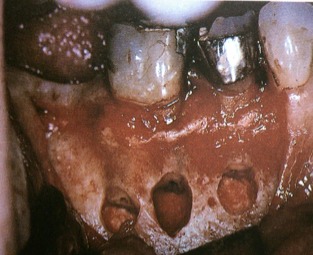

Category E is a condition where the apical pathology and the periodontal sulcus depth do join in a true combination periodontal/endodontic infection. The image below also shows the surgical view once the tissue has been flapped back.

Surgical View of a Category E

Category F is of course the worst periodontal condition for a tooth with no buccal bone at all and total attachment loss to the apex of the root. You can again see the image showing this surgical view with a total lack of buccal plate.

Surgical View of a Category F